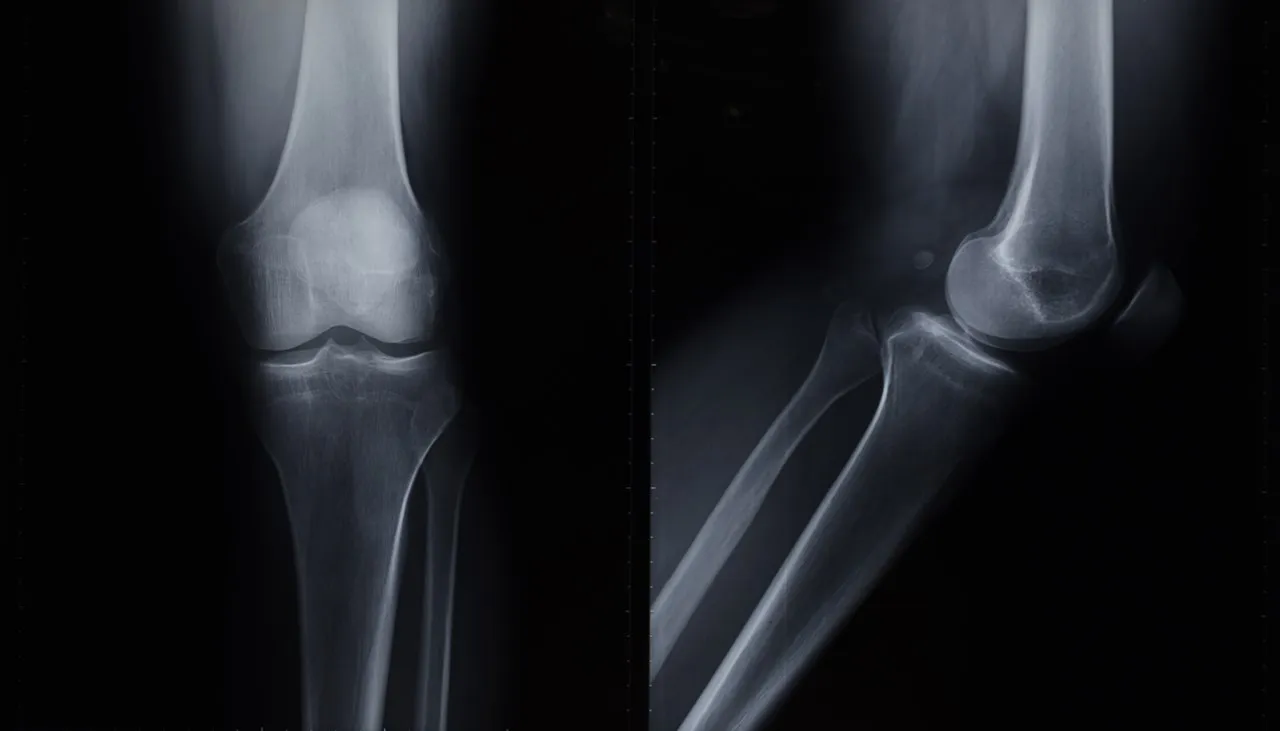

El proyecto, “Sistema basado en Inteligencia Artificial para la detección de osteosarcoma en imágenes de tomografía de fémur”, lo llevó a cabo en el Instituto Nacional de Rehabilitación Luis Guillermo Ibarra (INR) y consistió en desarrollar un software basado en Tecnología Computarizada para apoyar en el diagnóstico de osteosarcoma, el cáncer óseo primario más frecuente en infancias, adolescencias y adultos mayores.

Durante su presentación, explicó que actualmente no existe un caso de estudio o experimento que utilice un dataset de imágenes de fémur obtenidas mediante Tecnología Computarizada para la detección de este tipo de tumor maligno.

La metodología empleada por Emilio incluyó, en un principio, la selección, recuperación y preprocesamiento de imágenes de Tecnología Computarizada, asegurando un balance entre las clases a detectar (tejido sano y tumor), proceso que llevó a cabo en conjunto con radiólogos del INR para asegurar la confianza y precisión de los diagnósticos.

Posteriormente, el dataset se dividió en subconjuntos para ajustar los hiperparámetros, entrenar la red neuronal convolucional (CNN) y realizar una validación cruzada con el fin de optimizar el desempeño del modelo.